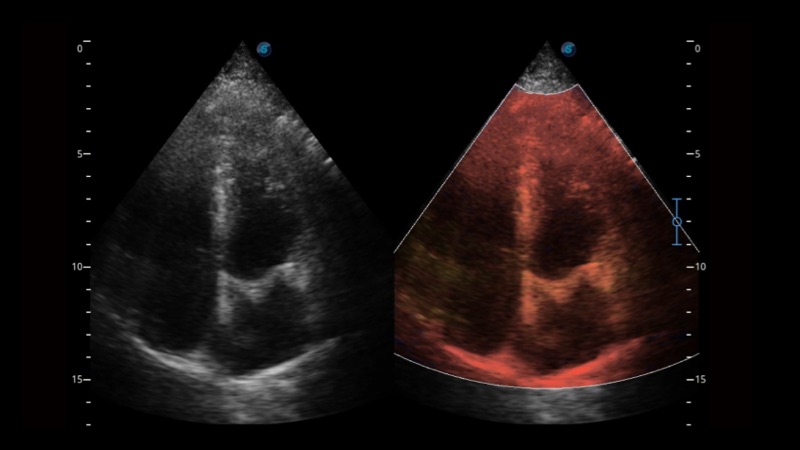

開立醫(yī)療通過不斷的技術(shù)創(chuàng)新,為大眾的生命健康提供持續(xù)關(guān)愛。P12 Plus采用全新一代超聲成像平臺(tái),新平臺(tái)旨在將真實(shí)還原組織解剖結(jié)構(gòu)作為首要目標(biāo)。平臺(tái)采用全新集成化硬件模塊,搭載新一代芯片,系統(tǒng)性能得到大幅提升,為您的診斷提供了豐富的臨床信息。優(yōu)異的圖像表現(xiàn),豐富的探頭配置,全面的應(yīng)用功能,為您日常診斷提供了可靠的助手。

彩色多普勒超聲診斷系統(tǒng)